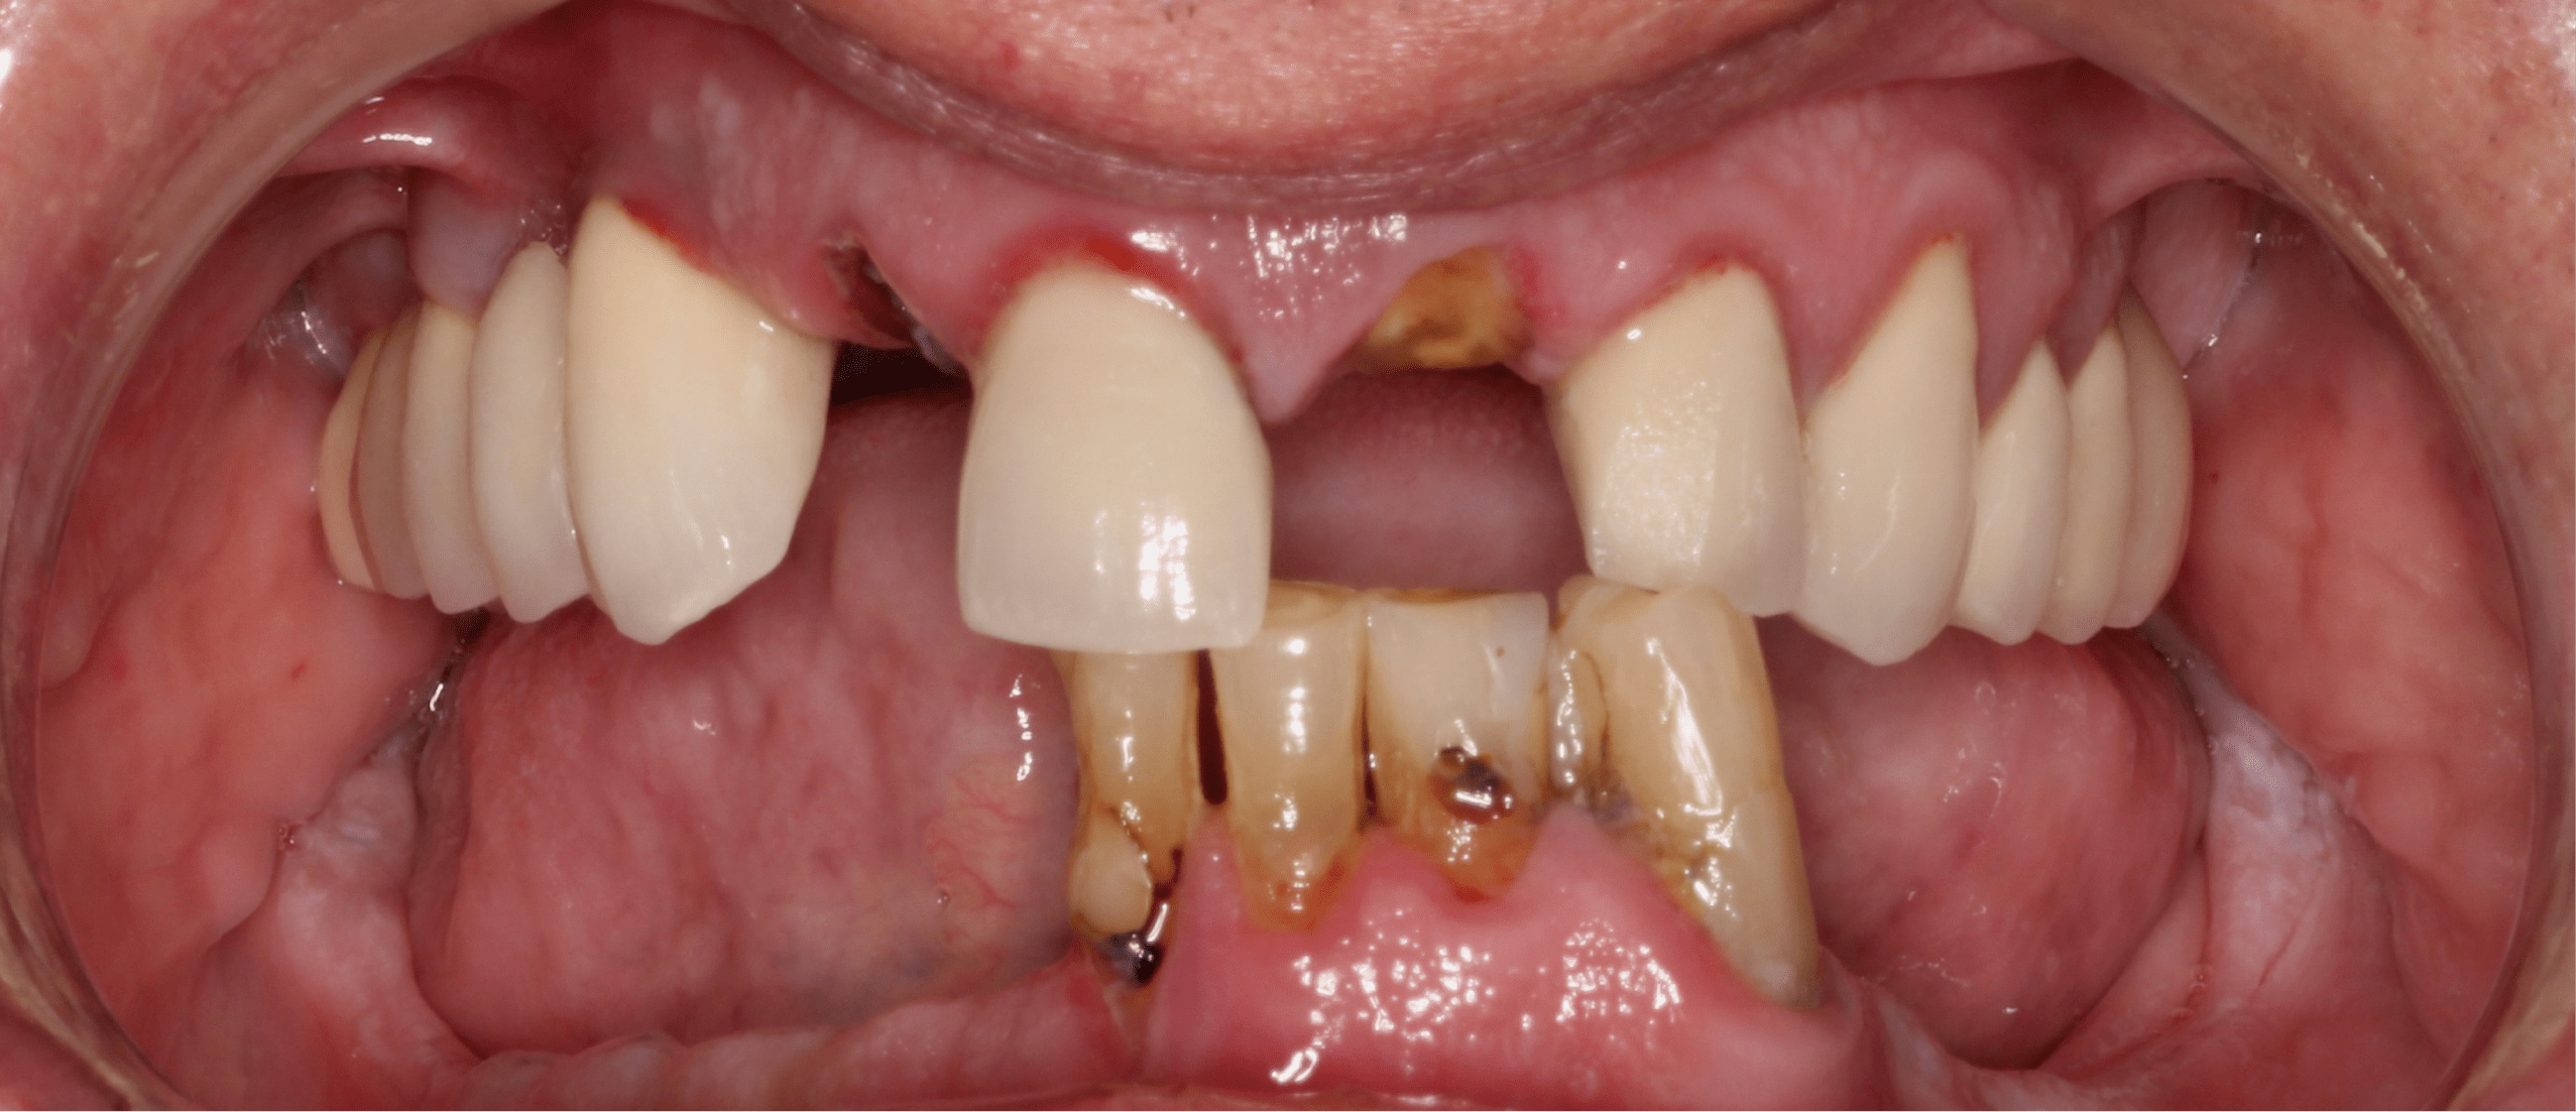

Patient Results